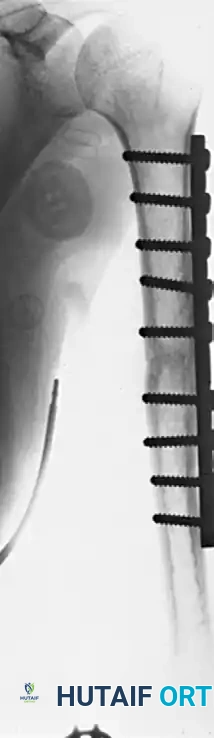

FIGURE 59-30 B: Solid union achieved 5 months after open reduction, rigid fixation with a nine-hole broad compression plate, and the application of autologous iliac bone grafts.

FIGURE 59-31 B: Postoperative radiograph demonstrating successful stabilization and healing after fixation with a locked intramedullary nail.